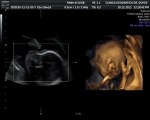

Celia 20 semanas

hace 14 años